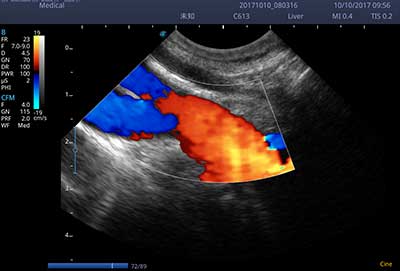

E3便携式彩色多普勒超声诊断系统拥有专业超声技术平台、高度集成化的硬件模块和结构设计、简便的操作流程、支持三探头接口全激活,兼顾了优质图像、轻便机身以及台便两用的临床使用需求。无论在常规超声科门诊检查,还是在急诊、麻醉、ICU、户外等各种应用场景。都能给您带来流程的操作体验。